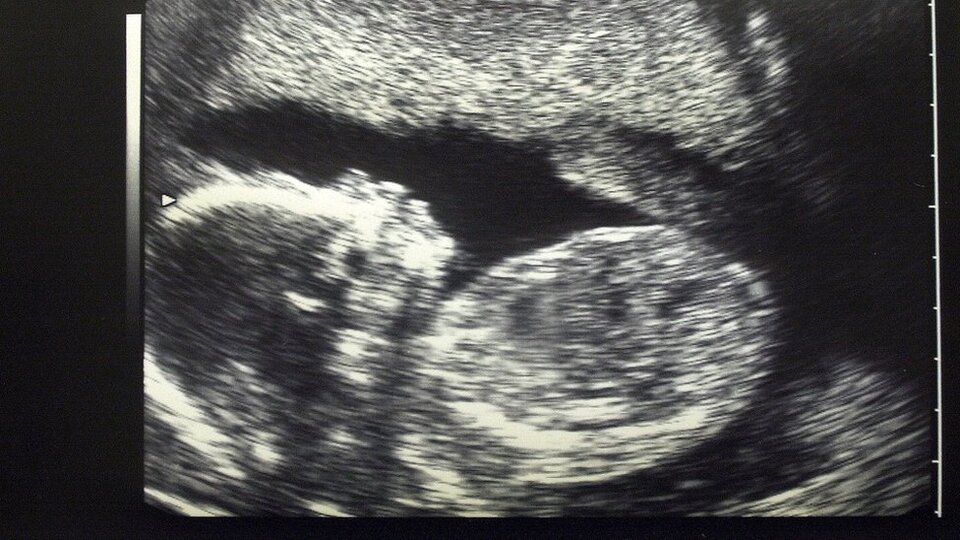

Belçika'da hamlie kadınlarla yapılan bir araştırmada plasentalarda (döleşi) hava kirliliği partikülleri bulundu.

Araştırma anne karnındaki bebeklerin de doğrudan trafik ve fosil yakıtların yakılmasından kaynaklanan kirliliğe maruz kaldıklarına işaret ediyor.

Belçika Hasselt Üniversitesi'nde yapılan araştırmada, sigara kullanmayan 25 kadının plasentaları incelendi.

Anne ve fetüsün dolaşım sistemlerini birbirinden ayıran bir organ olan plasenta, dokuların oluşması için gerekli olan besinleri ve oksijeni bebeğe taşıyor, ayırdığı atık maddeleri annenin vücuduna gönderiyor.

Araştırma, annenin soluduğu havadaki partiküllerin plasenta bariyerine sızabildiğini gösteren ilk çalışma olması açısından önem taşıyor.

İncelenen tüm plasentaların cenin tarafında, her bir milimetreküpte binlerce partikül bulundu.

Kirli havaya maruz kalmanın düşük, prematüre doğum ve bebeklerin zayıf doğmasına yol açabildiği biliniyor. Araştırma bunların sadece kirliliğin annelerde yol açtığı inflamatuar yanıttan değil, bizzat parçacıklardan kaynaklanabileceğine işaret ediyor.

Araştırma heyetinin başkanı Prof. Tim Nawrot, ceninde oluşacak hasarın, ömür boyu sürecek sonuçları olduğunu belirterek "Bu, hayatın en hassas dönemi. Çünkü tüm organlar oluşum aşamasında. Gelecek nesillerin korunması için onların kirli havaya maruz kalmasını önlememiz gerekiyor" dedi.